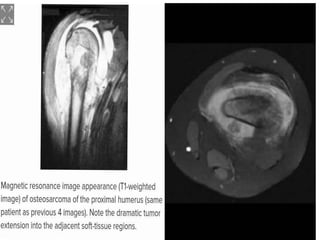

• MRI

• Single most important study for accurate clinical

staging using Enneking

• Can help demonstrate skip lesions

• Gives extent of disease and extracompartmental

involvement

• Axial view shows presence of neurovascular